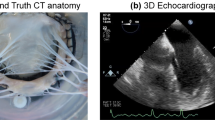

MV Fixation Validation Method

To evaluate the use of glutaraldehyde fixation to stiffen the MV and preserve the leaflet dimensions observed under pulsatile flow, a validation trial was performed. In its most refined form, the complete fixation and microCT imaging procedure as presented in this work was performed on five MVs (n = 5). Each MV in this trial was first imaged with 3D echo under pulsatile flow. Though the spatial resolution of this imaging modality is inferior to that of microCT, 3D echo is able to capture the coarse geometry of the MV at peak diastole under dynamic flow simulation. This was taken as the ground-truth diastolic MV geometry for the validation of the fixation method. Next, each valve was scanned by microCT in the unloaded state to capture the effect of surface tension on the valve. The MVs were then glutaraldehyde-fixed using the above protocol. Following fixation, the MVs were again imaged by microCT in the unloaded state. Dimensions of the MV leaflets (anterior leaflet area, A1 segment length, A2 segment length, A3 segment length, and P2 segment length) were measured on the peak diastolic frame of 3D echo and were taken as ground-truth. These measurements were then replicated on both the glutaraldehyde-fixed and unfixed microCT scans, and the measurement difference from ground-truth was found. An acceptable error threshold for all measurements was determined to be ±5% from ground truth.

Diastolic CT Geometry Validation

Finally, microCT and 3D echo were used to validate the fixation procedure for obtaining a physiologically accurate diastolic MV geometry. Summarized in Fig. 10, all leaflet length and area measurements from the glutaraldehyde-fixed microCT scan were found to be equivalent within ±5% to those measurements made on the peak diastolic frame of 3D echo (95% confidence). Without fixation, all length and area measurements were found to be significantly smaller than both 3D echo derived measurements and measurements from fixed microCT scans (p < 0.005). Furthermore, the standard deviations of these measurements were appreciably smaller after fixation, indicating not only improved accuracy and detail, but also improved consistency over previous methods.28

MicroCT scans of each MV (n = 5) in the diastolic state with- and without glutaraldehyde fixation are compared to the peak diastolic frame of 3D echo for the same MVs under pulsatile flow. Mean and 95% confidence interval are shown for the differences observed in identical measurements made on the diastolic microCT scan and on a mid-diastolic frame of 3D echo images. Anterior leaflet lengths (A1–A3), posterior leaflet length (P2) and anterior leaflet area (Area) were all found to be equivalent to within ±5% with 95% confidence between the glutaraldehyde fixed images and the dynamic 3D echo images (p < 0.05). Percent change of the above measurements from the 3D echo images to the unfixed microCT images was found to be significantly negative (p < 0.001), revealing substantial MV shrinkage in the range of 20–30% when imaging without fixation.